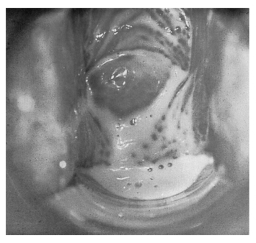

1.4.2.7.3三、临床表现

1.4.2.7.4四、诊断要点